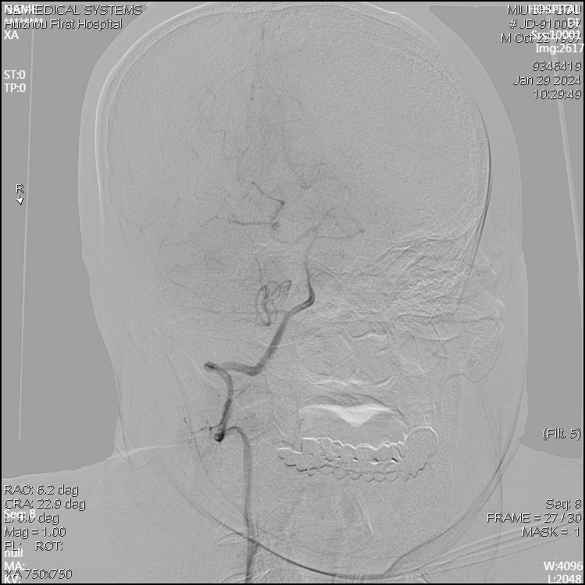

急诊DSA未见畸形血管。

急诊DSA(右侧颈内正位)

右侧颈外侧位

右侧椎动脉正位片

右侧椎动脉侧位片